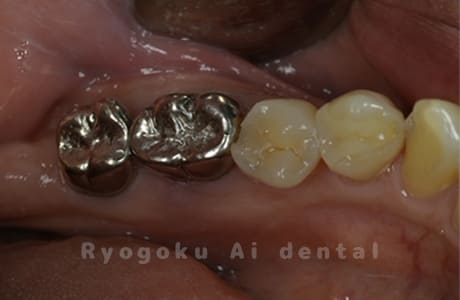

Case10

-

- 原因

- 右下6番 重度カリエス

- 治療内容

- 右下8を右下6へ移植に自家歯牙移植

- 治療期間

- 約1か月半

- 治療費用

- 220,000円

右下の銀歯が外れかかっているとのことでご来院された患者様です。虫歯が大きく、かつ歯が割れており、保存不可能と判断し、親知らずの移植を行いました。

<リスク・副作用>

治療後、痛みや違和感、出血、腫れなどが出る事があります。喫煙者、糖尿病などの方の場合、歯が生着しない場合があります。